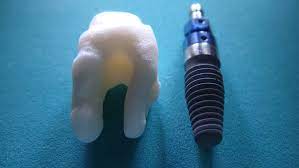

임플란트는 충치, 잇몸병으로 인해 상실된 치아나 사고와 종양으로 없어진 치아의 기능과 미용을 복원하기 위해 치료하는 시술을 말합니다. 임플란트는 통증, 움직임이 거의 없는 나의 치아와 같은 느낌을 주며 입안의 뼈가 건강하다면 80세 이상까지도 치료가 가능한 시술이라고 할수 있습니다.

임플란트 시술비용

임플란트 시술 비용은 임플란트 종류, 시술 부위, 치아 상태 등에 따라 달라집니다. 일반적으로 국산 임플란트의 경우 1개당 평균 100~200만원, 수입 임플란트의 경우 200~300만원 정도 합니다.

임플란트를 해야하는 이유

틀니는 사용 중에 떨어질 우려가 있고, 잇몸뼈의 소실로 인해 추가적인 가공이 필요한 단점이 있습니다. 반면, 임플란트는 잇몸뼈의 손상을 최소화하면서 안정적으로 고정되어 오랜 기간 사용 가능한 특징을 가지고 있기 때문입니다. .